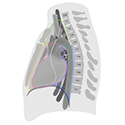

Anatomical Illustrations